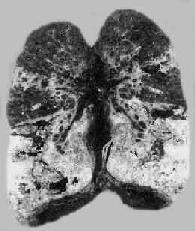

3.慢性纤维空洞型肺结核为成人慢性肺结核的常见类型,多在浸润型肺结核形成急性空洞的基础上发展而来。病变特点是在肺内有一个或多个厚壁空洞形成。同时在同侧肺组织,有时也可在对侧肺组织,特别是肺下叶可见由支气管播散引起的很多新旧不一、大小不等、病变类型不同的病灶,部位愈下病变愈新鲜。空洞多位于肺上叶,大小不一,呈不规则形,洞壁厚,有时可达1cm以上。洞内常见残存的梁柱状组织,多为有血栓形成并已机化闭塞的血管。空洞附近肺组织有显著纤维组织增生和肺膜增厚(图18-8)。镜下,洞壁分层:内层为干酪样坏死物质,其中有大量结核杆菌;中层为结核性肉芽组织;外层为增生的纤维组织。由于病情迁延,病变广泛,新旧不等,肺组织遭到严重破坏,可导致肺组织的广泛纤维化,最终演变为硬化型肺结核,使肺体积缩小、变形、变硬、肺膜广泛增厚并与胸壁粘连,可严重影响肺功能。

慢性纤维空洞型肺结核病(冠状切面)

图18-8 慢性纤维空洞型肺结核病(冠状切面)

右上叶,左上叶上部和左下叶上部都有厚壁空洞形成;肺门淋巴结无结核病变